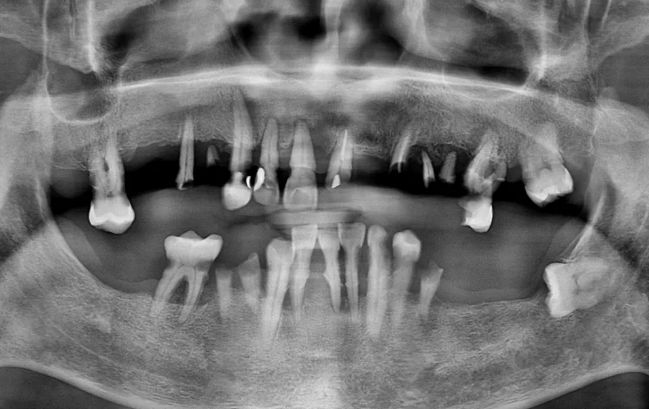

50대 남성, 원데이 전체 임플란트 18개 식립